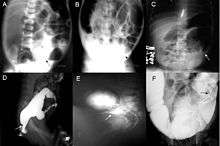

Definitive diagnosis is made by suction biopsy of the distally narrowed segment.[12] A histologic examination of the tissue would show a lack of ganglionic nerve cells. Diagnostic techniques involve anorectal manometry,[13] barium enema, and rectal biopsy. The suction rectal biopsy is considered the current international gold standard in the diagnosis of Hirschsprung's disease.[14]

Radiologic findings may also assist with diagnosis.[15] Cineanography (fluoroscopy of contrast medium passing anorectal region) assists in determining the level of the affected intestines.

Hirschsprung’s disease is a congenital disorder of the colon in which certain nerve cells, known as ganglion cells, are absent, causing chronic constipation.[33] The lack of ganglion cells is in the myenteric plexus (Auerbach's Plexus), which is responsible for moving food in the intestine. A barium enema is the mainstay of diagnosis of Hirschsprung’s, though a rectal biopsy showing the lack of ganglion cells is the only certain method of diagnosis.